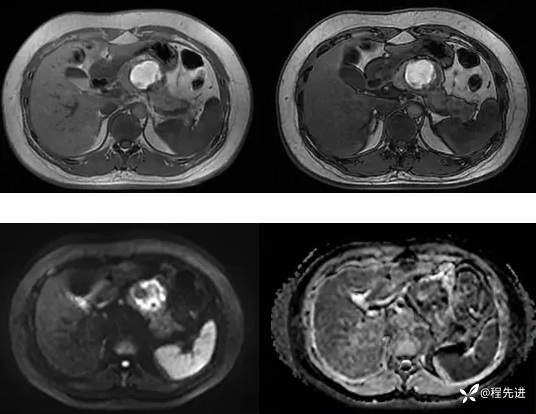

T1、T2:

同反相位,DWI、ADC: